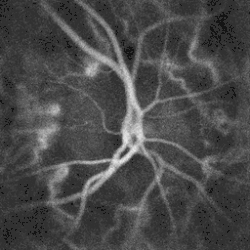

![]() Pulsatile blood flow in the central retinal artery revealed by laser Doppler holography | |